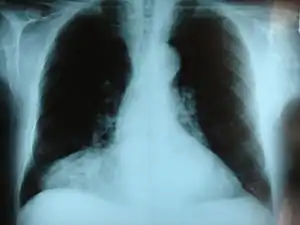

Morgagni hernia seen on a chest radiograph.

Morgagni hernia